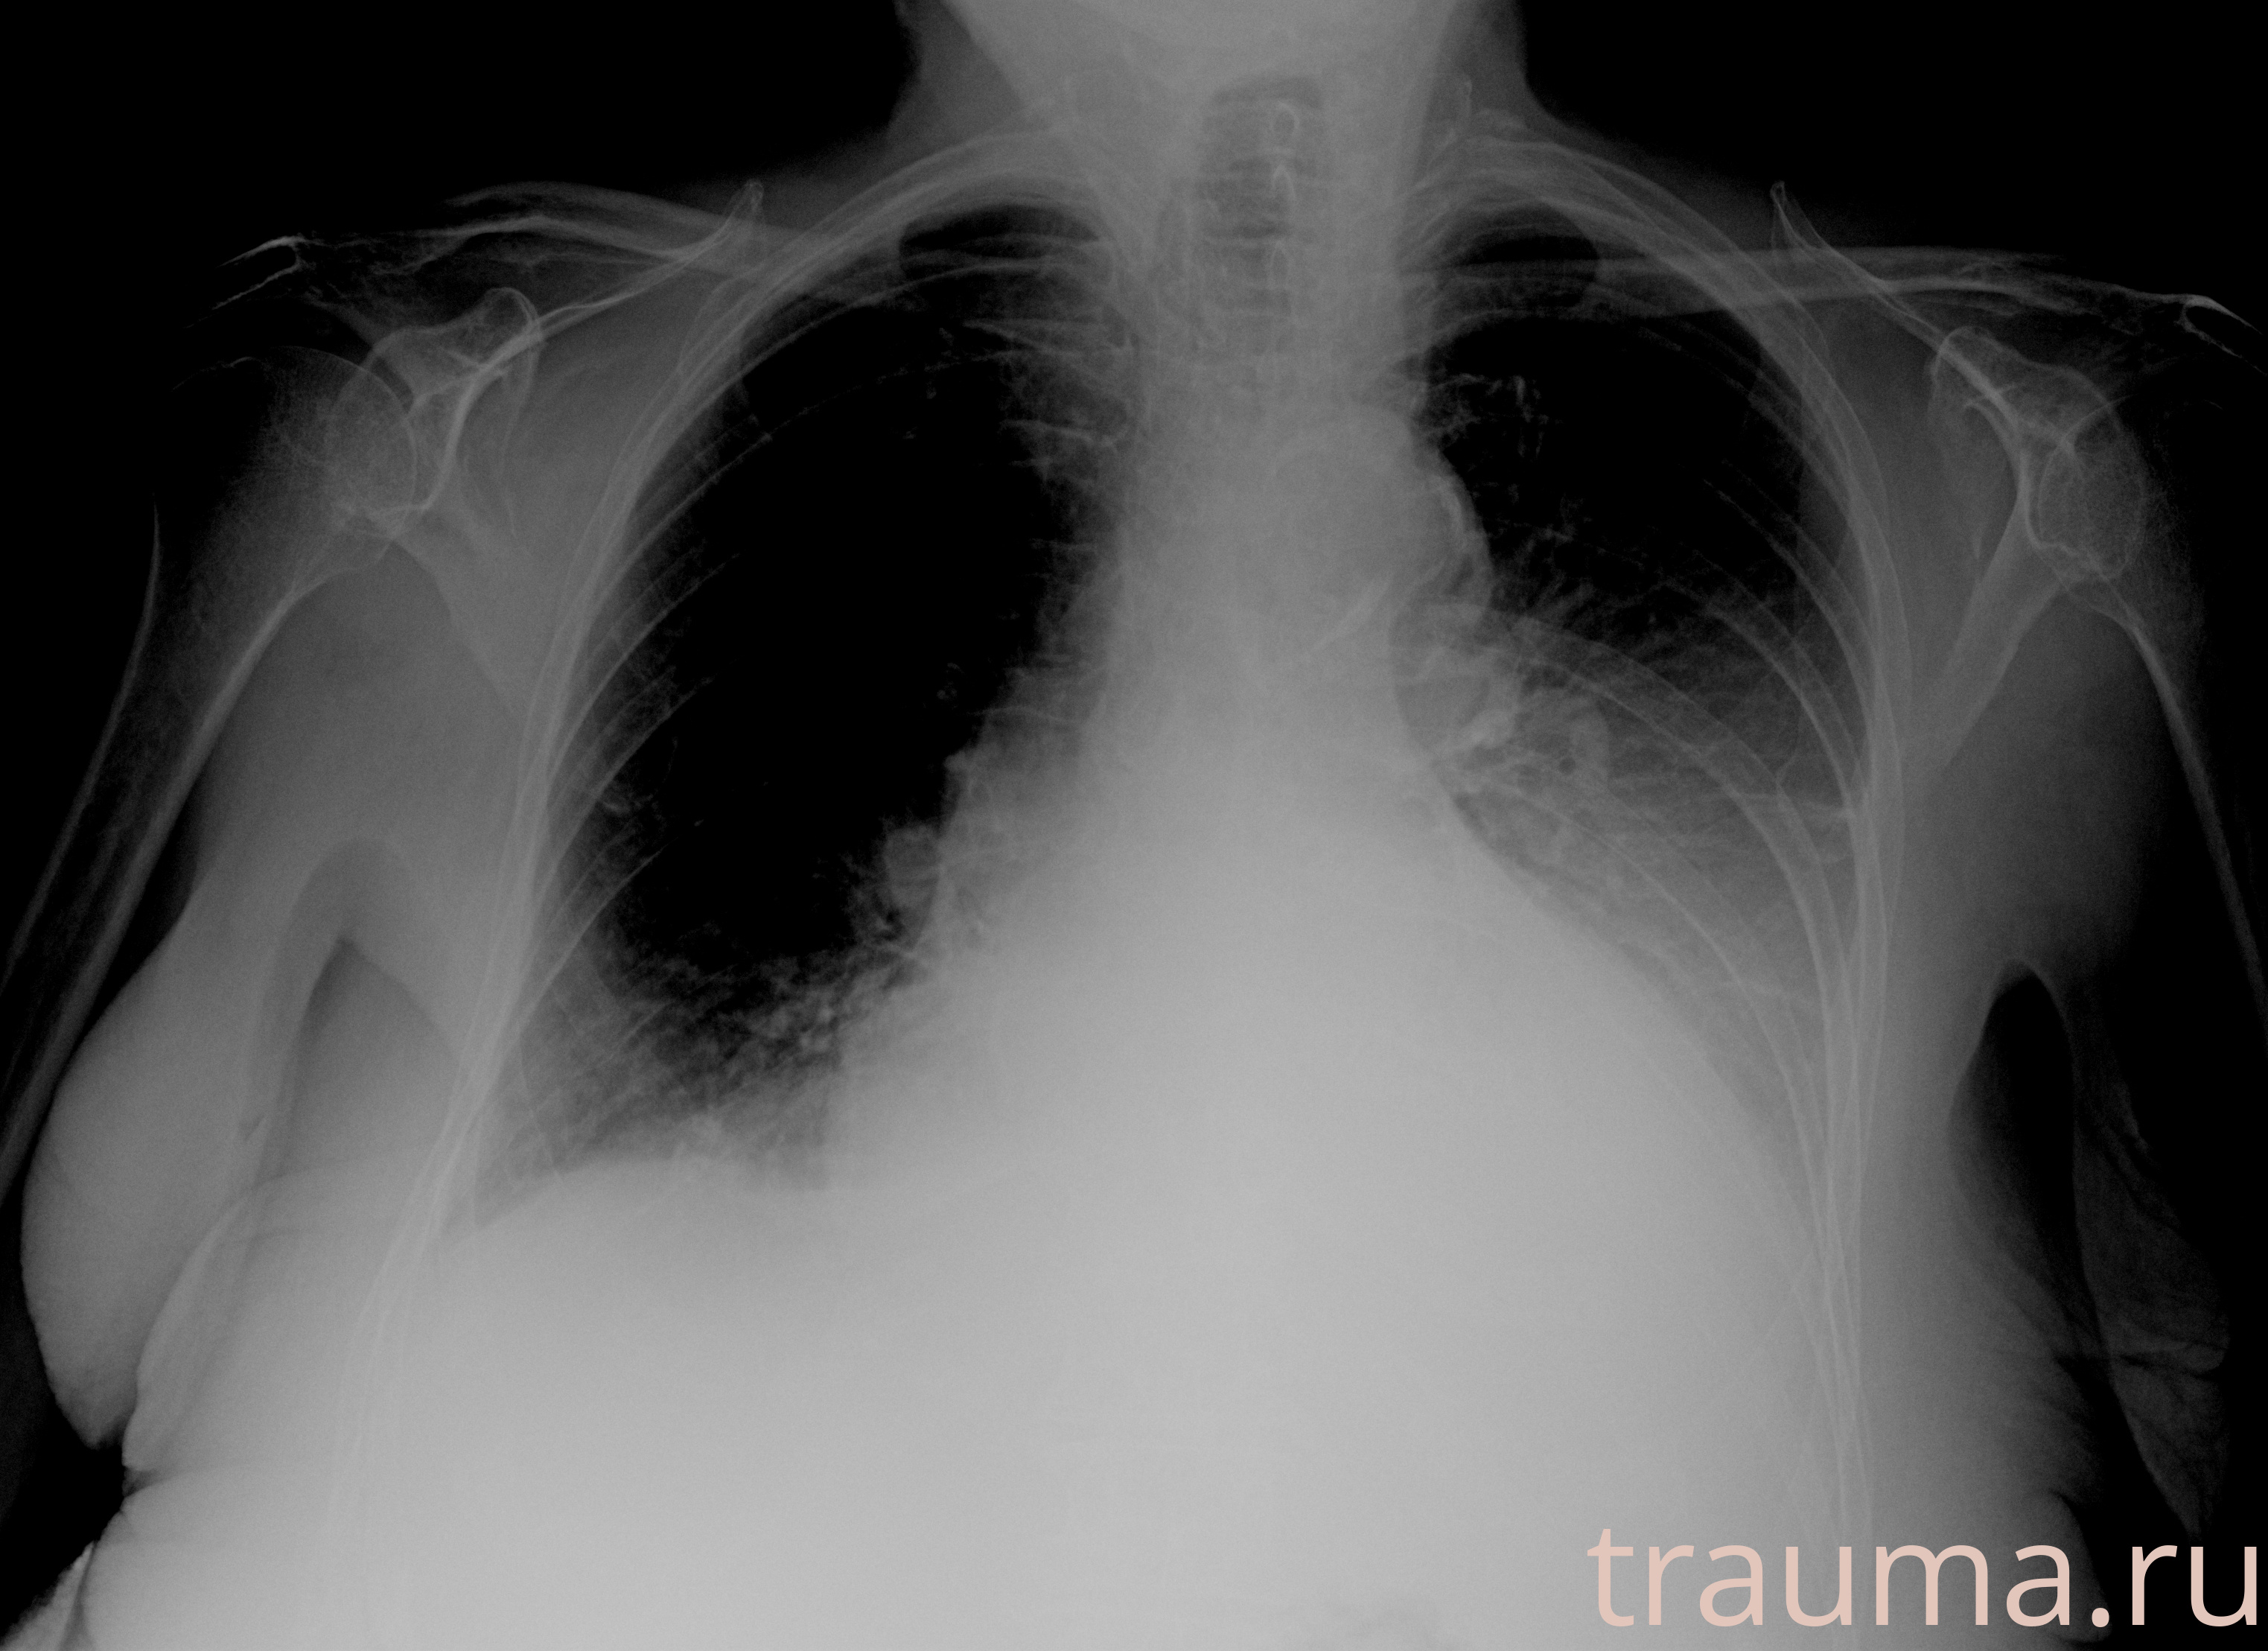

Рентгенограммы

Рентген на дому: по вашему адресу приезжает врач-рентгенолог, травматолог-ортопед с мобильным рентгеновским аппаратом, проводит диагностику травмы или заболевания, делает необходимые рентгенограммы, дает рекомендации по дальнейшему лечению. Получить качественные снимки в домашних условиях возможно благодаря уникальной методике, разработанной МосРентген Центром для института  Склифосовского

при переломе шейки бедра и пневмонии от компании МосРентген Центр - партнера Института имени Склифосовского